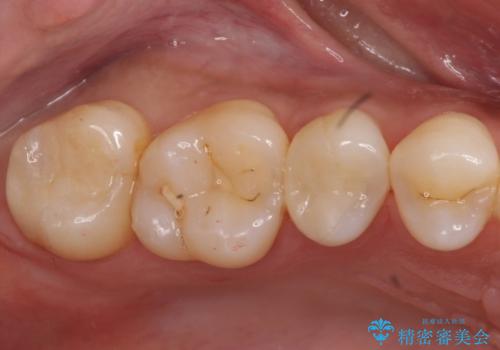

- 上の奥の虫歯をセラミックインレーで修復しました。

治療前後の写真をお見せして説明したところ、非常に喜んでいただきました。

特に自費のインレーの適合(歯にぴったり合っている)はとても良く、虫歯になりにくいです。

高価なようで、実は将来のことを考えた歯を残す治療の第一歩です。